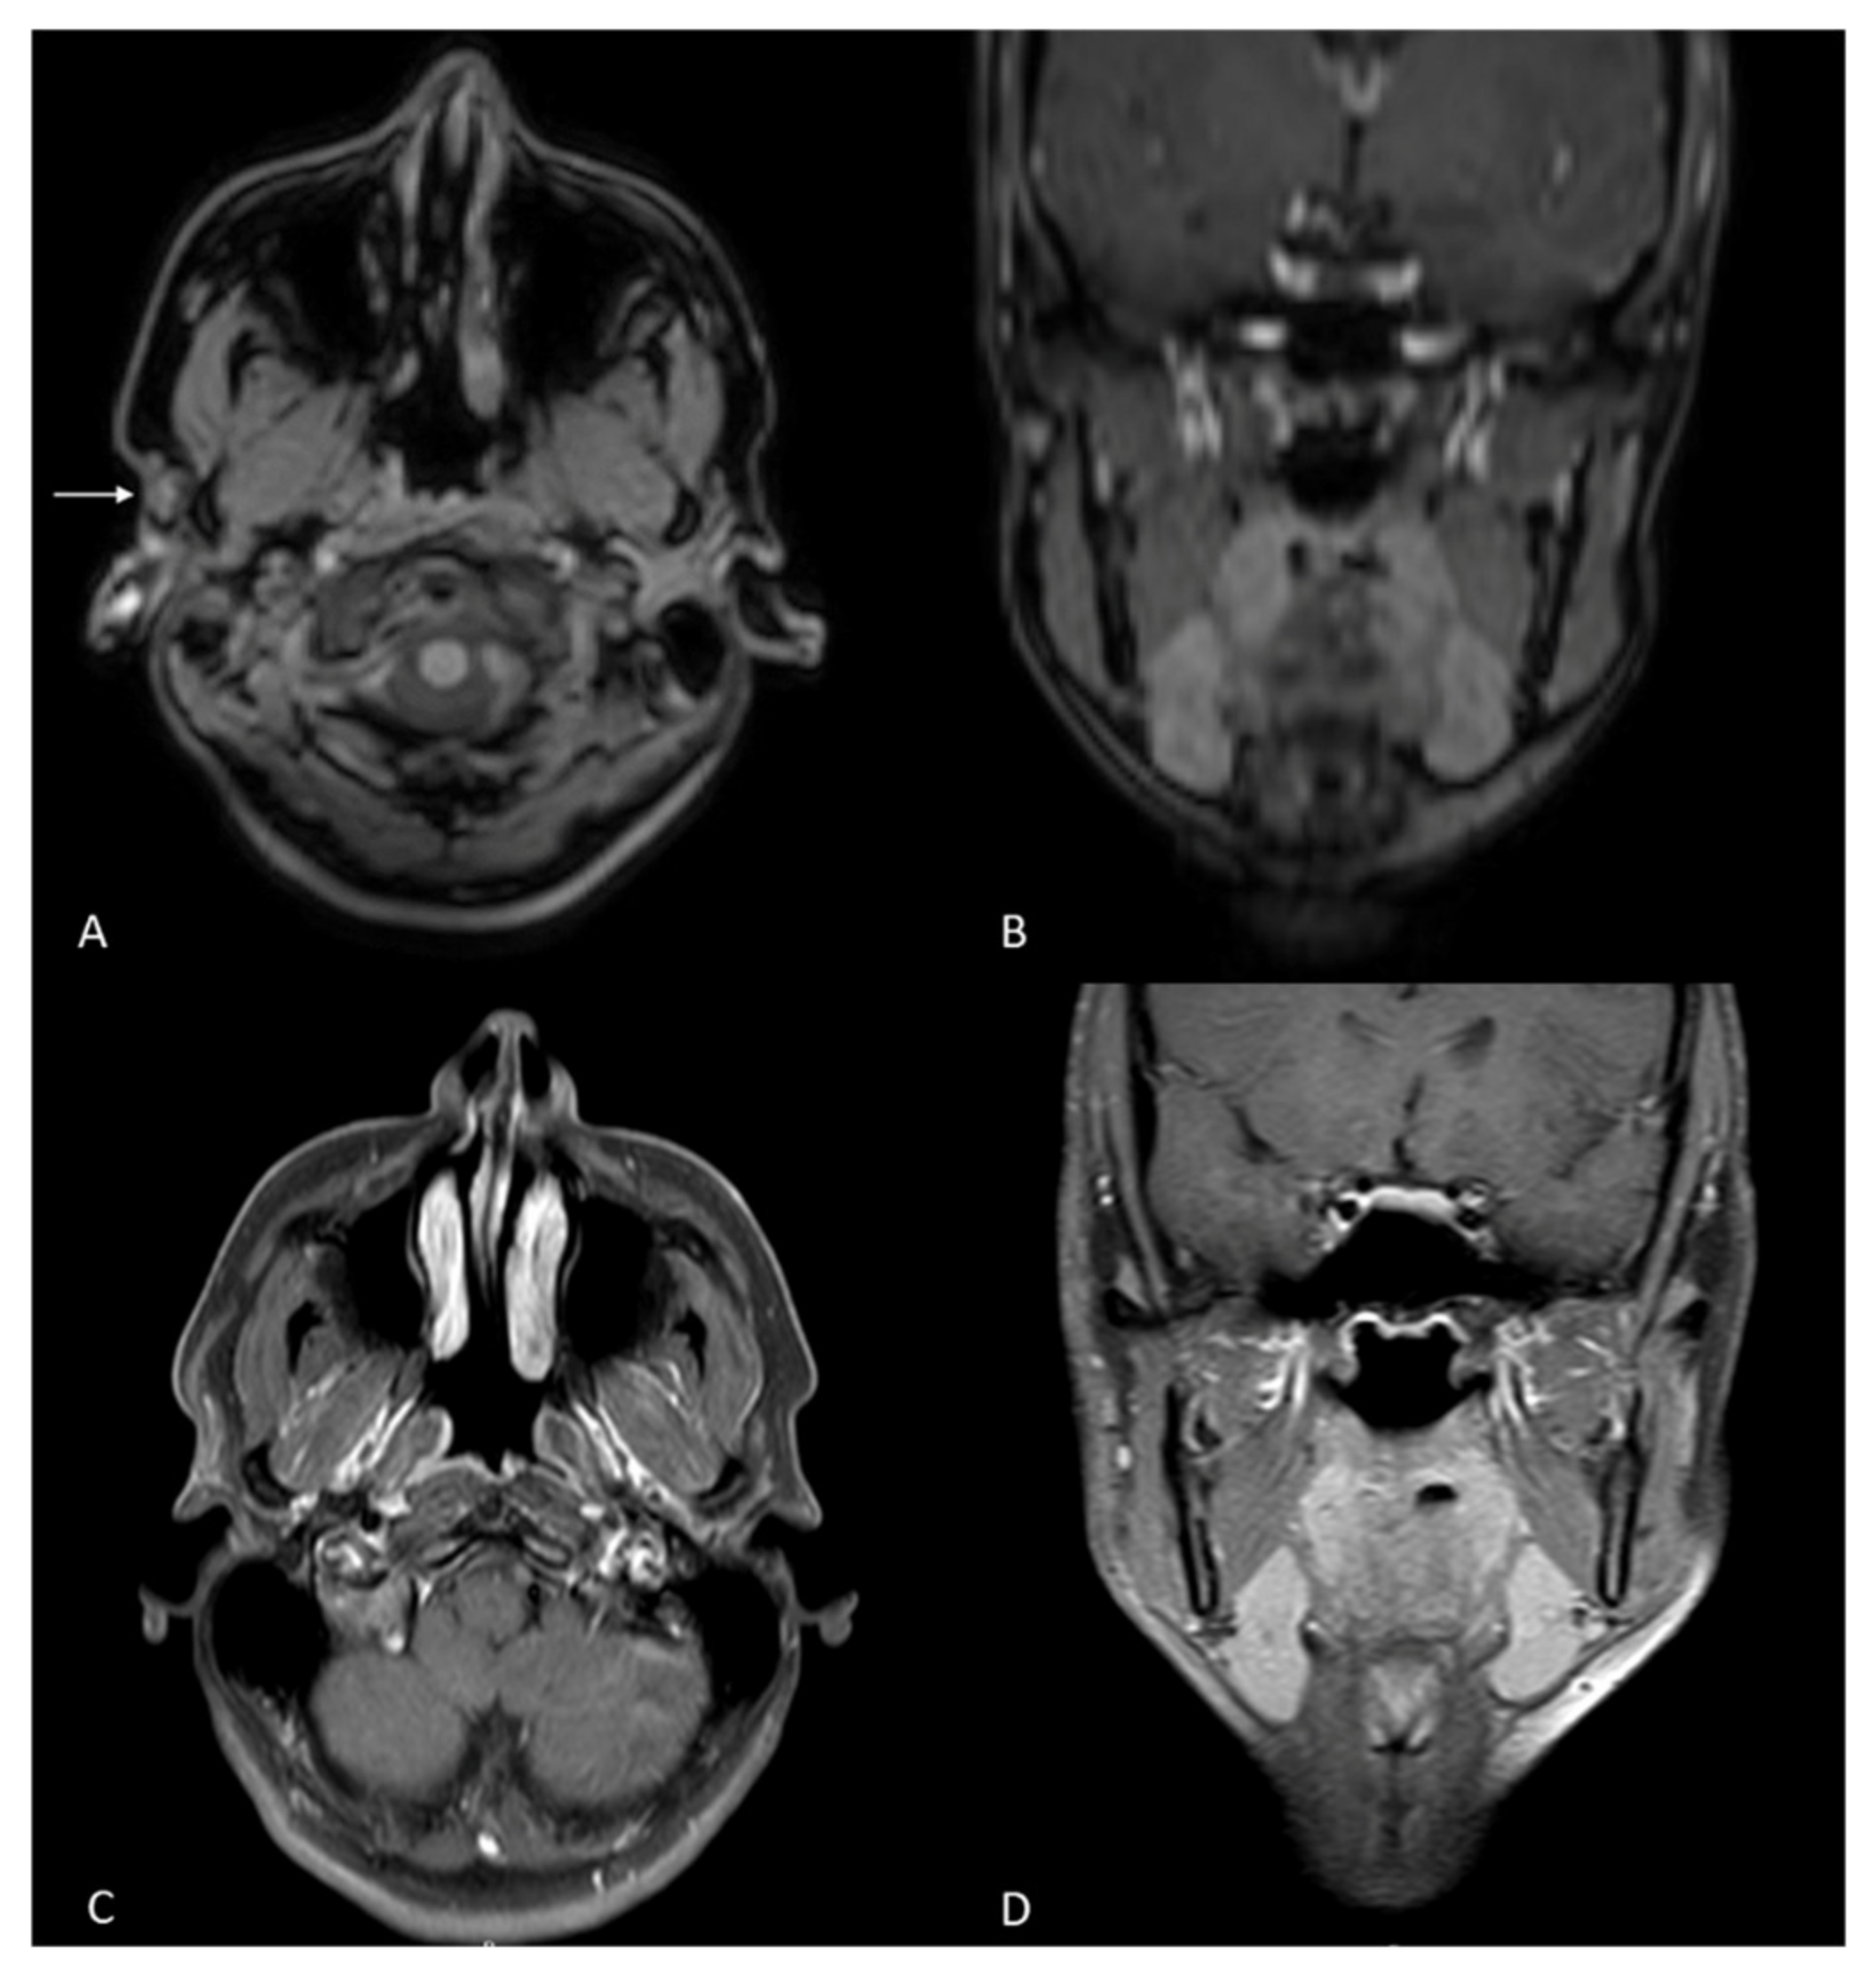

2. Case Report